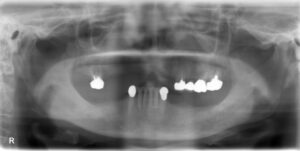

上下9本欠損症例

BEFORE AFTER 61歳女性/上下9本欠損/インプラント埋込手術 【治療内容】 上顎前歯は重度のむし歯で残根状態…